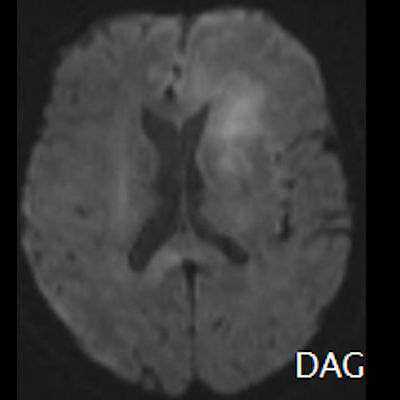

- (C) Difüzyon ağırlıklı görüntülerde sol frontaldeki kitle lezyonunda difüzyon kısıtlama bulgusu (oklar) mevcut olup perfüzyon MRG’de rCBV haritasında belirgin perfüzyon artışı izlenmemektedir (ok).

- MRG’de, lenfomalar tipik olarak T2A sekanslarda hipointens olup DAG’de belirgin difüzyon kısıtlanması gösterirler.

- T2 sinyali belirgin düşük olgularda b=1000 görüntülerde hipointens görünüm izlenebilir ve T2 kararması (T2 black-out) etkisi olarak adlandırılan bu durum yanlış yorumlamalara yol açabilir. Bu nedenle gerçek difüzyon kısıtlamasını değerlendirmede ADC haritaları daha güvenilirdir.

- Perfüzyon MRG’de düşük-orta düzey CBV değerleri izlenir. Lenfomalarda düşük CBV değerleri, kötü prognoz göstergesidir.